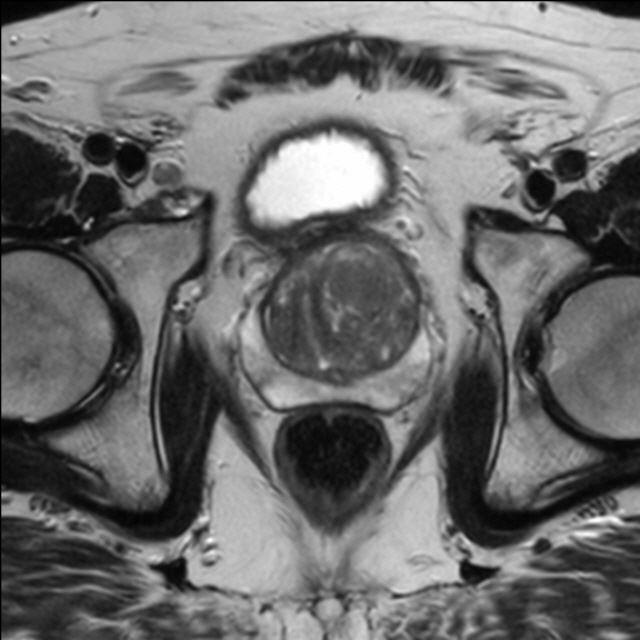

Prostata (mpMRT)

Die multiparametrische MRT der Prostata (mpMRT) bietet eine gute Möglichkeit, mittels bildgebender Diagnostik die Lokalisation, die Ausdehnung und eventuelle Aussaat eines Prostata-Karzinoms darzustellen.

Bei fehlender Darstellung des Tumors im Ultraschall oder vergeblichen Biopsien kann die MRT als Problemlöser eingesetzt werden: Sie zeigt dem Urologen, wo eine weitere Biopsie die Diagnose sichern kann. Außerdem kann die MRT bei sehr ausgedehnten Tumoren einen Überblick über die Beteiligung der Nachbarorgane verschaffen und Absiedlungen (Metastasen) entdecken.